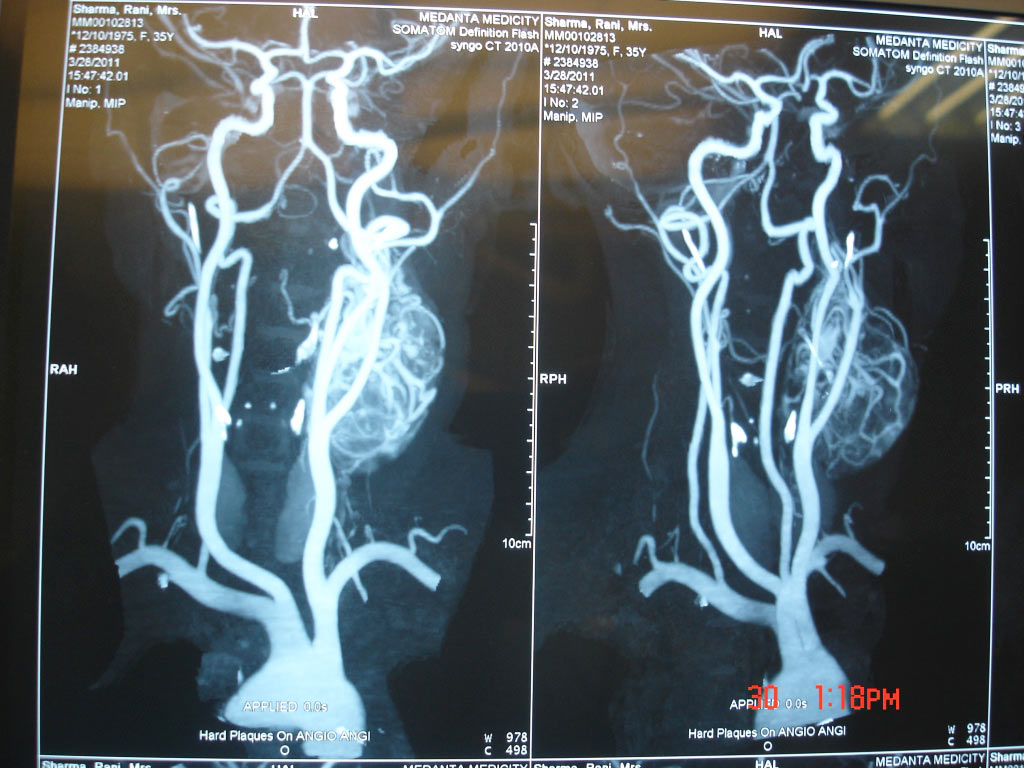

Uterine Artery Embolization